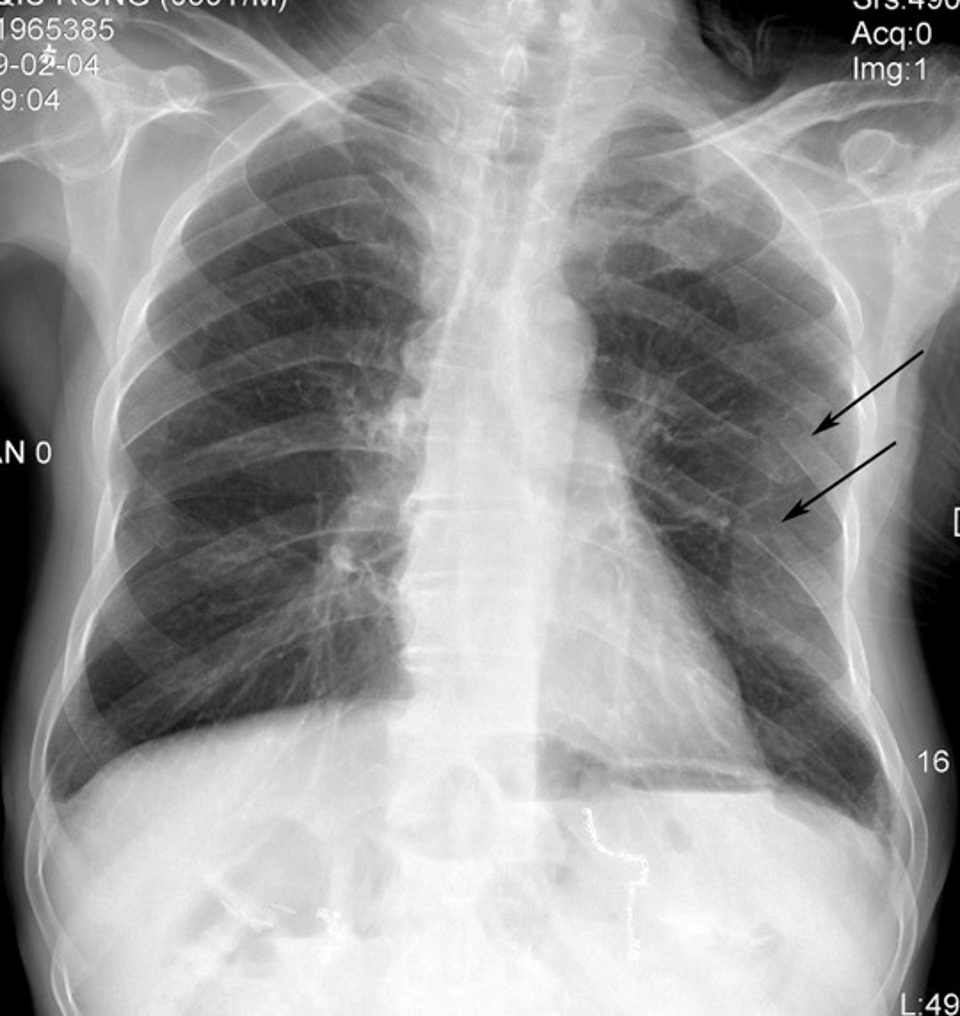

This patient has a history of left mastectomy; what should you be cautious about when interpreting this CXR?

R breast accentuates pulmonary vessels at base of R lung — with mastectomy history, these accentuations can be mistaken for RLL infiltrates & the darker left lung can be misinterpreted as hyperinflation.